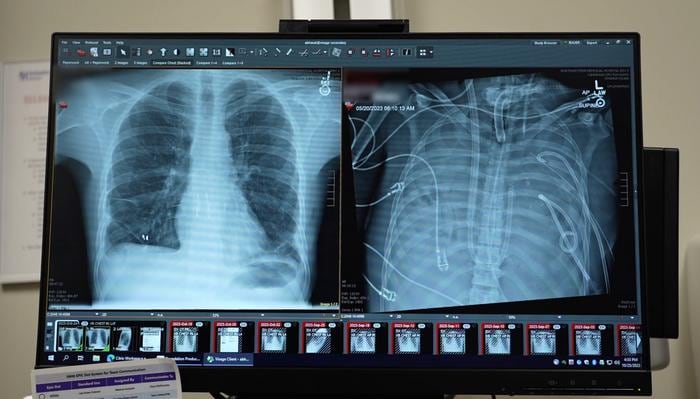

Durante 48 horas, el paciente permaneció sin pulmones, con el tórax vacío y conectado únicamente al sistema artificial. El equipo médico vigiló de cerca su evolución y, al confirmarse la mejoría, logró ingresar al paciente en la lista de trasplantes. Dos días después, se realizó el trasplante doble de pulmón. Más de dos años después del procedimiento, el paciente mantiene una vida normal y sus pulmones funcionan correctamente.

El análisis de los pulmones extraídos reveló que el daño era irreversible. Los investigadores encontraron cicatrices y destrucción del tejido a nivel molecular, lo que, según el especialista, constituye una “prueba biológica de que algunos casos de SDRA no tienen posibilidad de recuperación sin trasplante”.